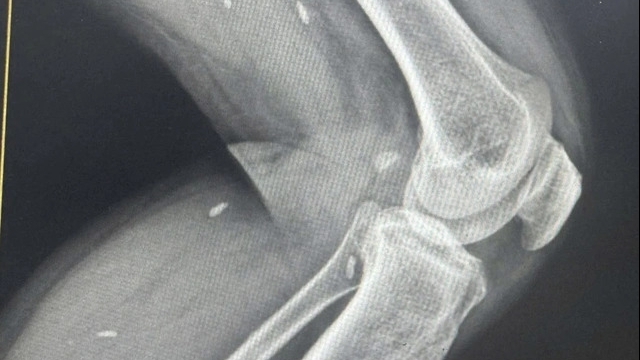

![]() |

| Khối u chiếm toàn bộ phần gan phải trên phim CT scan bụng |